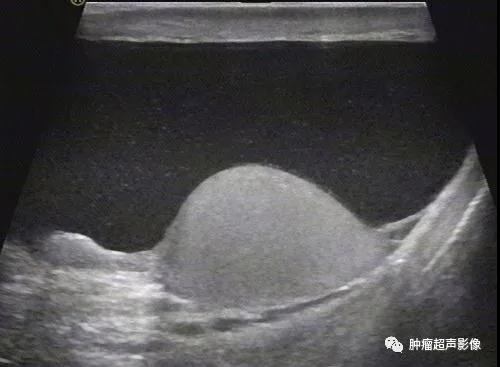

2、精索鞘膜积液:无回声位于睾丸上方或腹股沟区(一面靠水),呈圆形或梭形,边界清晰,光滑,位置可高可低,阴囊增大不明显。

精索鞘膜积液:一面靠水